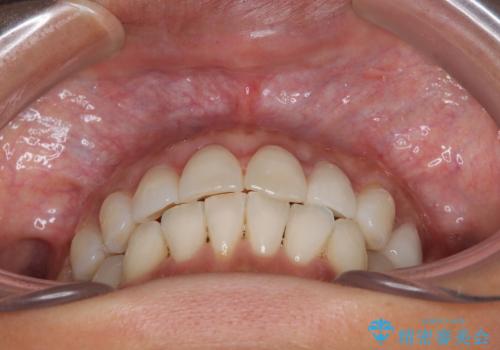

- 目立つ銀歯やむし歯、前歯のデコボコを気にして来院された患者様です。

デコボコはある程度改善できれば良いとのことでしたので、インビザラインの廉価版を用いて矯正治療を行うこととしました。

むし歯治療は、症状のある歯を矯正治療前に処置し、概ね歯列が整ったところで残りのは全て処置し、最後にインビザラインで歯列を仕上げることで、無駄なく治療を進めて行くこととしました。

しっかりと装着時間を守ってくださり、来院のタイミングに合わせてインビザラインの装着期間を調整するなど、協力いただいたおかけで、1年半の期間で全てを終えることができました。